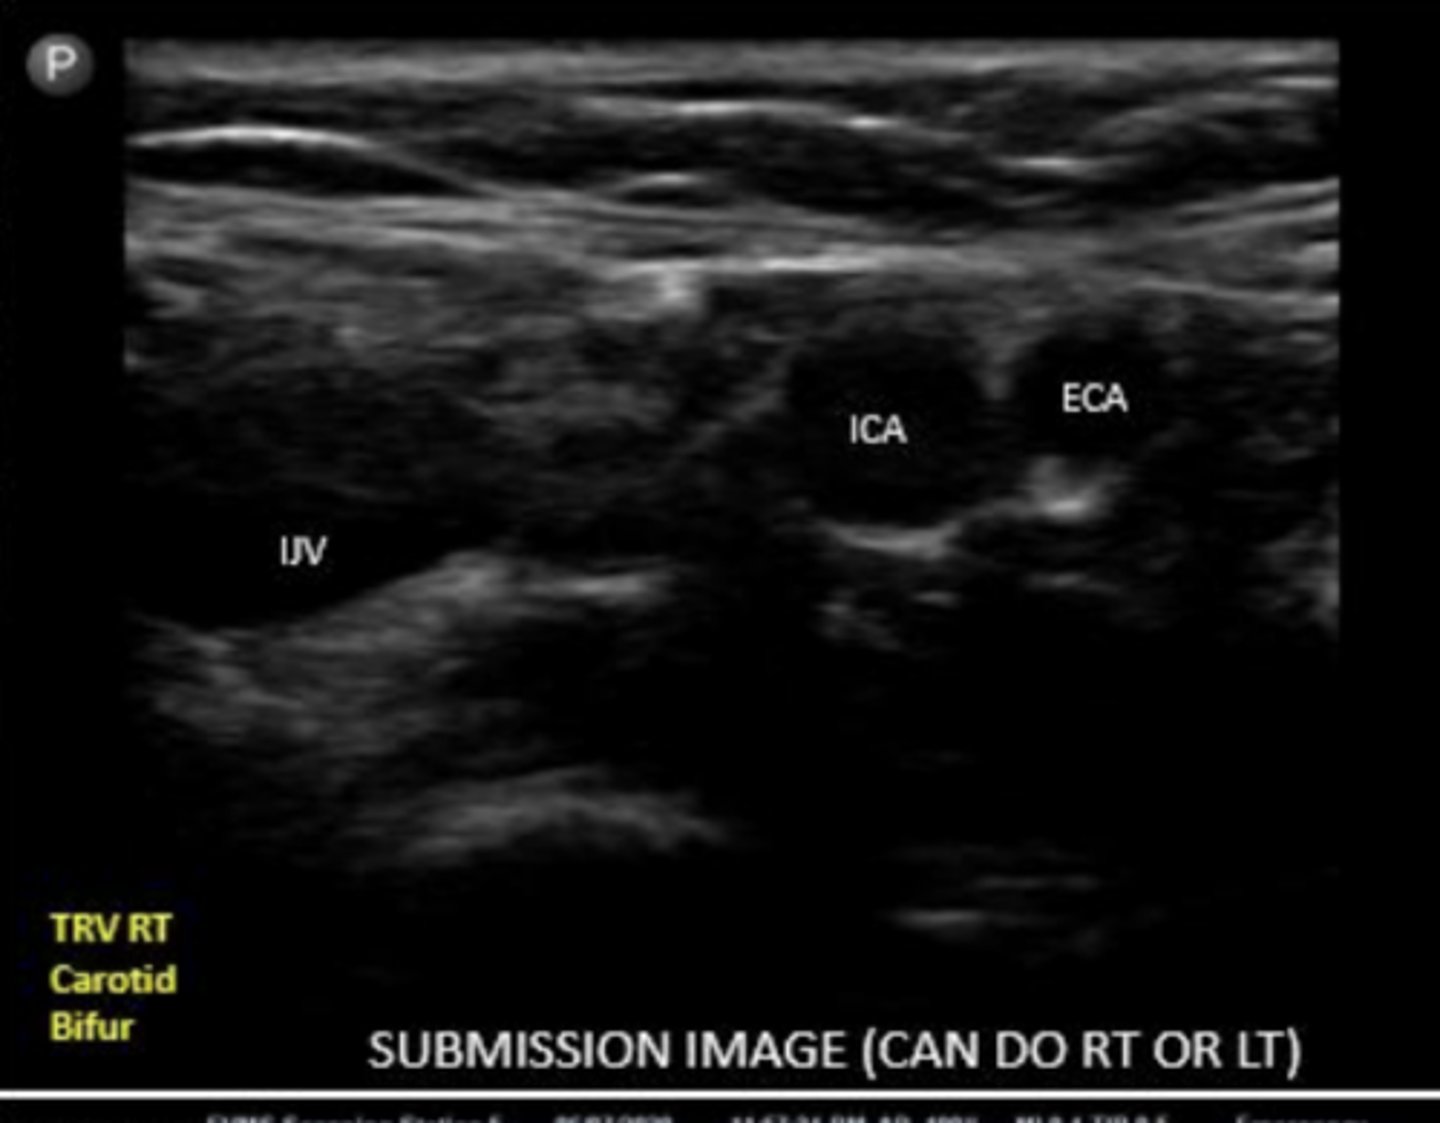

what will you see before the bifurcation into ECA and ICA

carotid bulb

ICA

internal carotid artery

ECA

external carotid artery

ECA is typically more _____ and ______

ECA is usually more anterior and medial

ICA is typically more ____ and _____

ICA is usually more posterior and lateral

When scanning the carotid bifurcation, is the IJV the most medial or lateral structure?

lateral